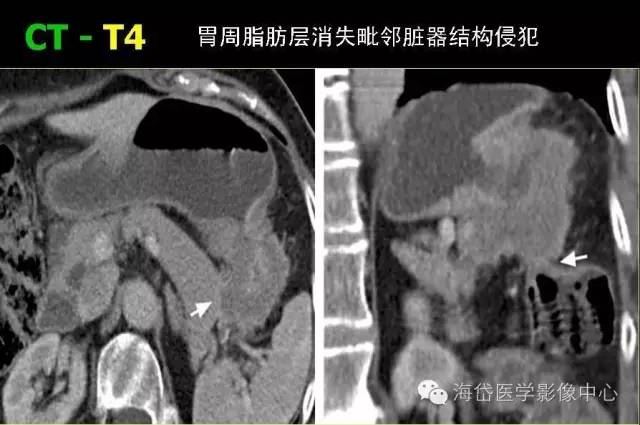

T4 T4a 腫瘤侵透漿膜;T4b 腫瘤侵及鄰近器官。